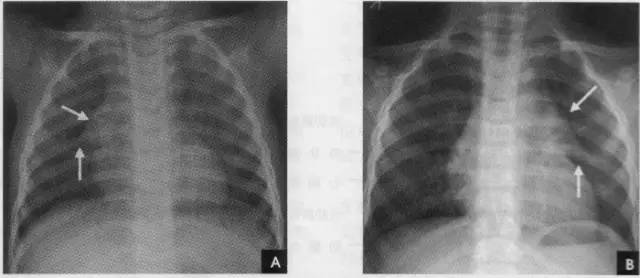

2、横裂又称水平裂,约70%的人正、撼位胸片均可显影。在正位片上表现为右中肺野横行细线状阴影,从第6肋腋部水平自外向内延伸.并止于肺门外lcm处。可向上或向下倾斜10:左右或略成曲线;在侧位片上,横裂起白斜裂中部,向前呈水平方向走行达前胸壁。其位置的改变可作为判断肺体积变化的标志(如上图)。

纵隔的分区对确定纵隔病变的部位和分析病变性贡有重要意义。分区的方法有多种,一般采用九分区法,即在侧位胸片上将纵隔划分为前、中、后夏上、中、下共九个区。前纵隔系胸骨之后,心脏、升主动脉和气管之前的狭长三角形区域,中纵隔相当于心脏、主动脉弓、气管和肺门占据的范围,食管前缘为中、后纵隔的分界线,食管以后和胸椎旁沟 l为后纵隔;自胸骨柄、体交界处至第4胸椎下缘连一水平线,其上为上纵隔,其下至肺门下缘的水平线(相当于第4前肋端至第8胸椎下缘的连线)为中纵隔,肺门下缘的水平线以下至膈为下纵隔(如上图)。后前位胸片上,纵隔在两肺之间形成致密阴影,隙气管和主支气管可以分辨外,其余结构间无明显对比,只能看到其与肺部邻接的轮廓。正常时因胸腔两侧压力相等,纵隔阴影居中,呼吸时无左右移动。儿童在2岁以下胸腺生长速度较纵隔快,在后前位胸片上常见一侧或两侧纵隔阴影增宽,边缘锐利,通常自上纵隔开始,向下逐渐增大向肺内凸出,下端成角,使增大的胸腺呈三角形,这是典型表现,遵骑踩影酷似船帆,故亦称“船帆征”,尤以呼气时明显(如下图)。